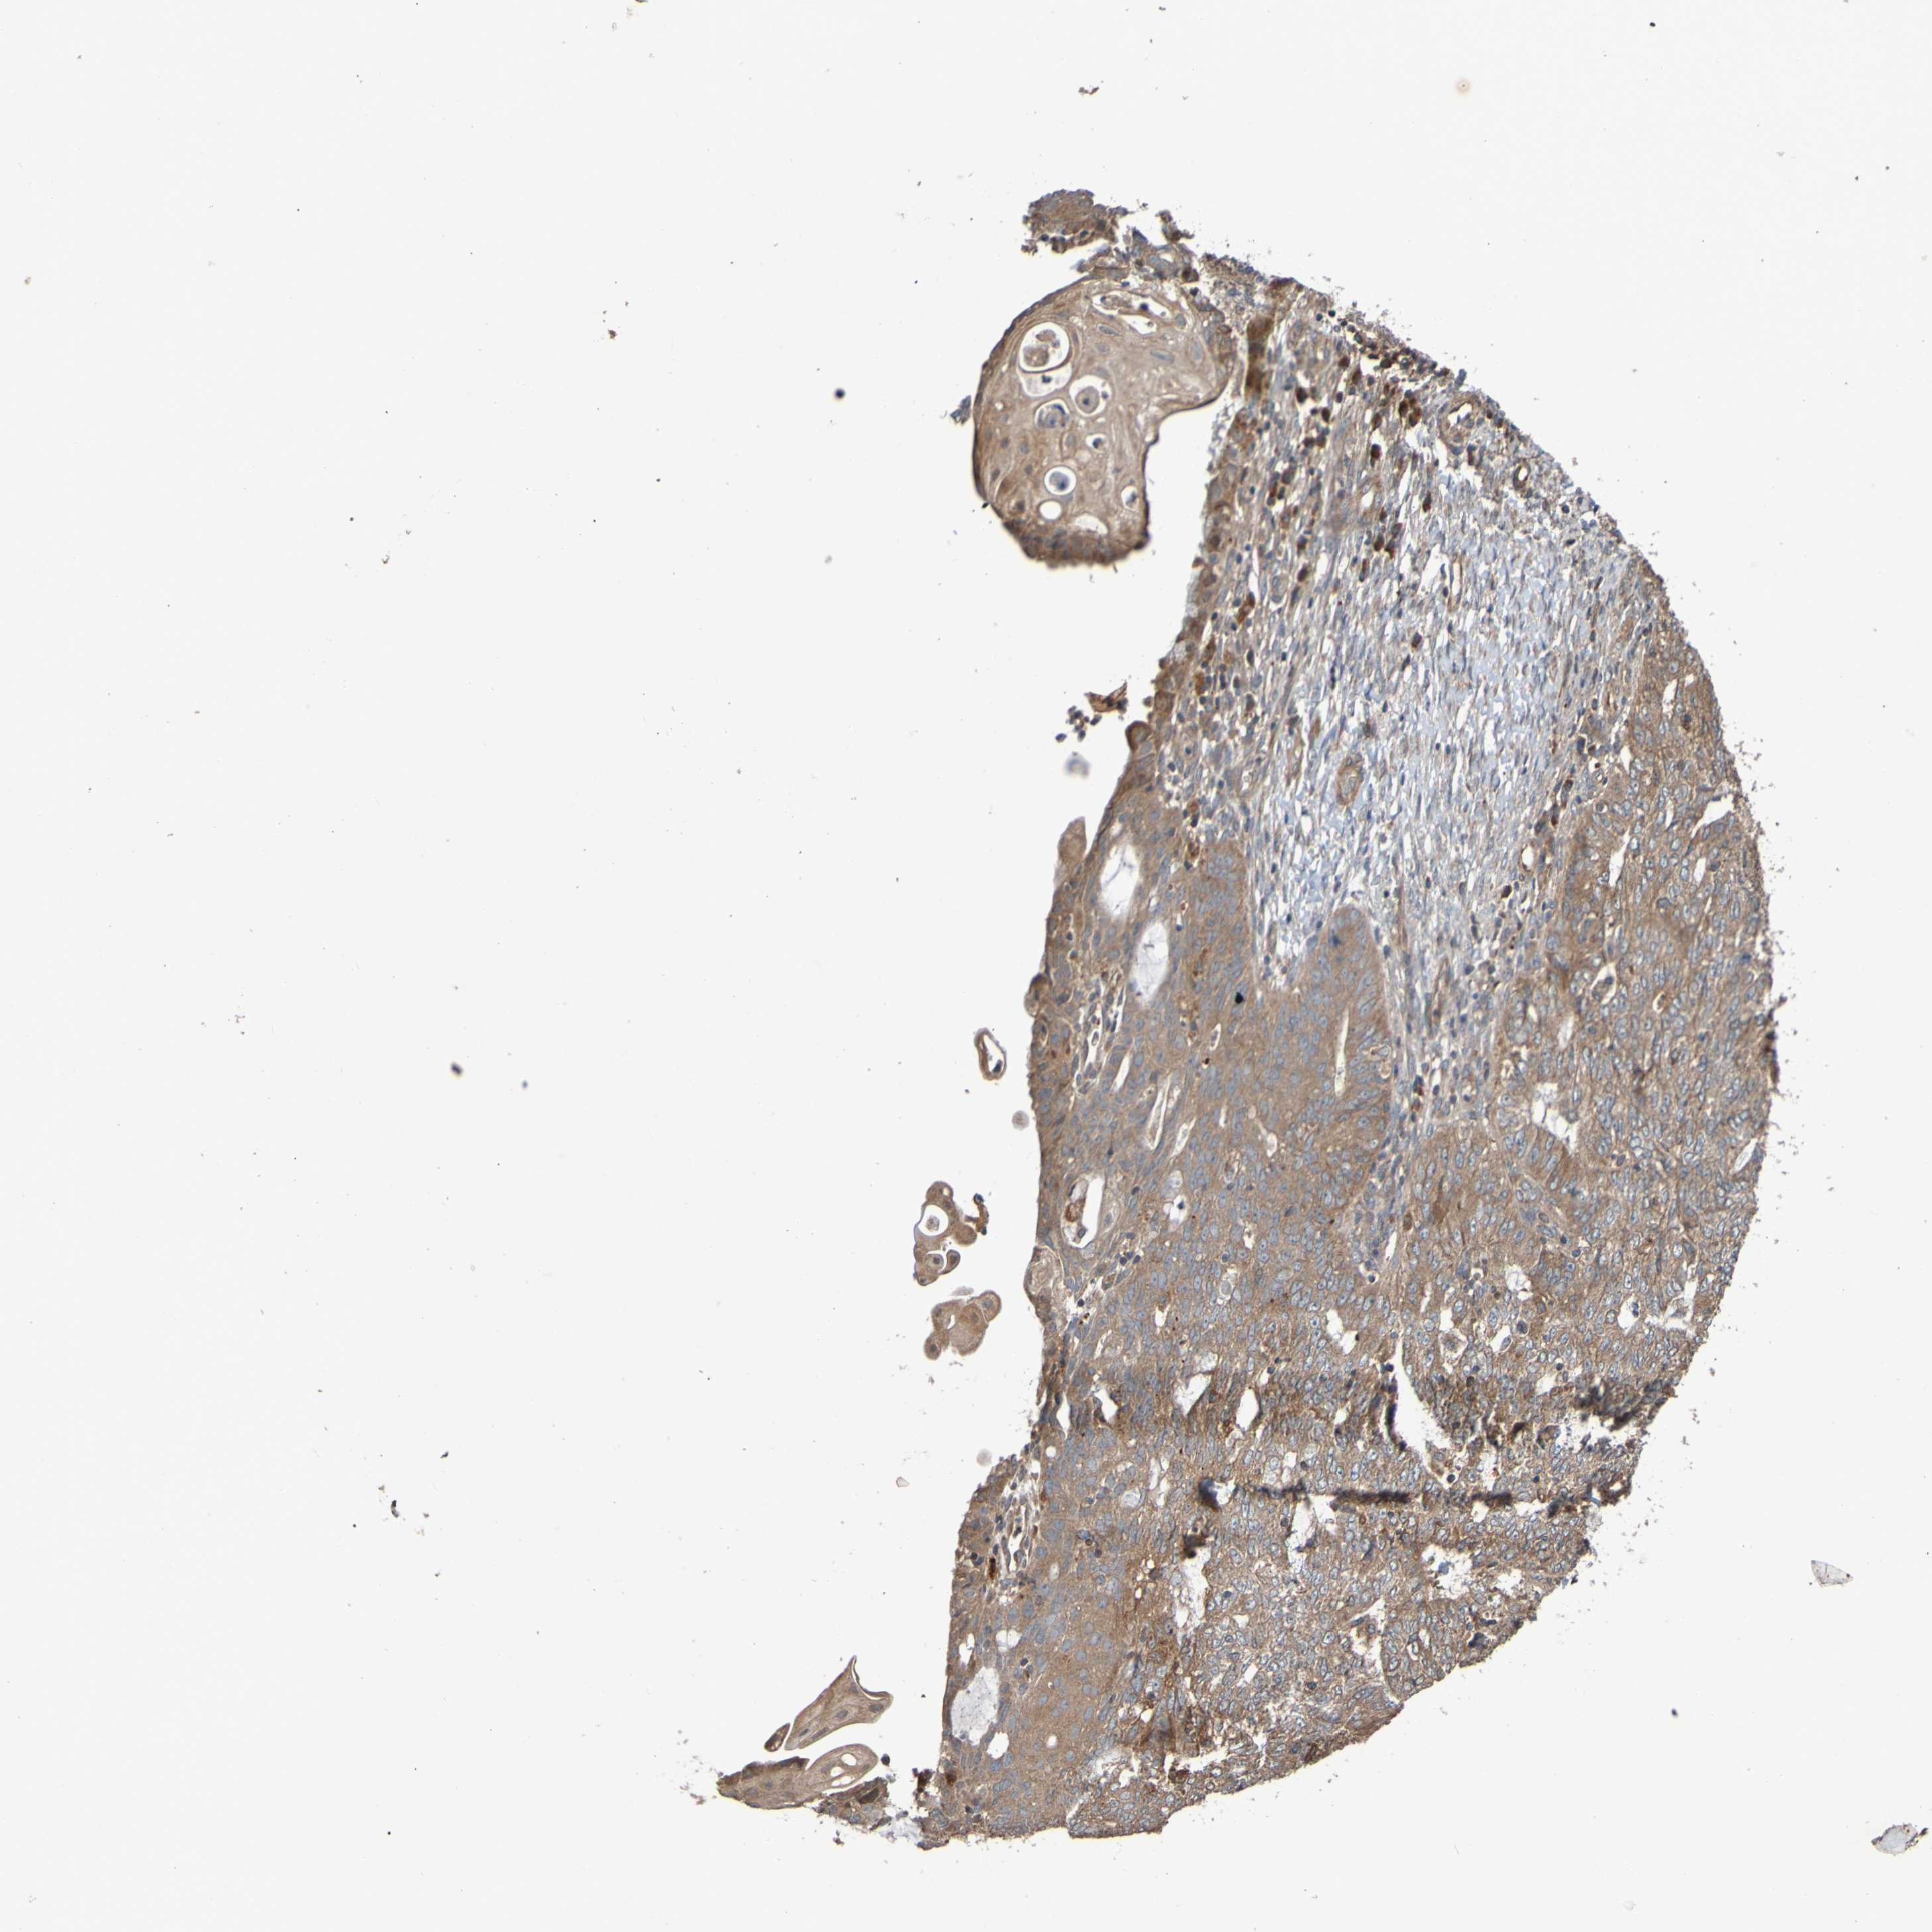

ENDOMETRIAL CANCER - Protein expressioni

A mouse-over function shows sample information and annotation data. Click on an image to view it in a full screen mode. Samples can be filtered based on level of antibody staining by selecting one or several of the following categories: high, medium, low and not detected. The assay and annotation is described here.

Note that samples used for immunohistochemistry by the Human Protein Atlas do not correspond to samples in the TCGA dataset.

Antibody stainingi

Antibody staining in the annotated cell types in the current human tissue is reported as not detected, low, medium, or high, based on conventional immunohistochemistry profiling in selected tissues. This score is based on the combination of the staining intensity and fraction of stained cells.

Each image is clickable and will lead to virtual microscopy that enables deeper exploration of all samples and also displays staining intensity scores, fraction scores and subcellular localization as well as patient and tissue information for each sample.

Antibody CAB010911

Staining

High

Medium

Low

Not detected

Intensity

Strong

Moderate

Weak

Negative

Quantity

>75%

75%-25%

<25%

None

Location

Nuclear

Cytoplasmic/membranous

Cytoplasmic/membranous,nuclear

Adenocarcinoma, NOS